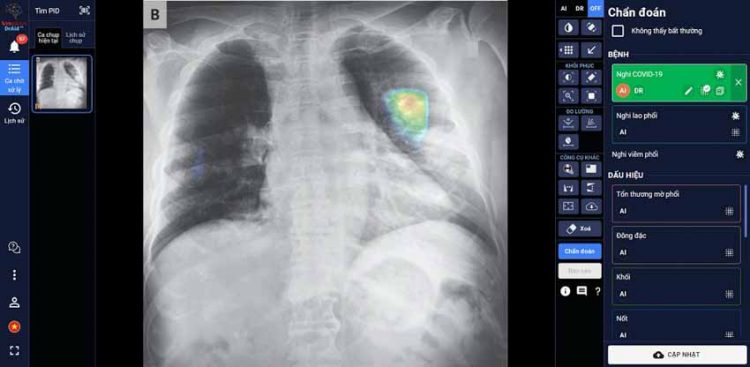

“DrAid for Radiology” – AI Trợ lý Bác sĩ cho Chẩn đoán hình ảnh y tế là sản phẩm đầu tay của VinBrain và cũng là sản phẩm AI hoàn chỉnh đầu tiên của y tế Việt Nam ra mắt phiên bản đầu tiên vào ngày 14-6-2020. Sản phẩm có khả năng phát hiện, sàng lọc trên 21 dấu hiệu bất thường và bệnh lý về phổi – tim – xương trong vòng 5 giây với độ chính xác trên 89%; đồng thời có thể chia sẻ kết quả chẩn đoán thông qua QR code hoặc đường link. Đặc biệt, sản phẩm có khả năng tự cảnh báo Covid-19, kể cả các trường hợp không có triệu chứng hoặc tổn thương phổi nhẹ dựa trên X-quang ngực thẳng, kết hợp cùng xét nghiệm PCR giúp nâng cao độ chính xác, giảm thiểu tình trạng âm tính giả… DrAid cũng nổi bật với tính năng “Hỏi ý kiến Bác sĩ thứ 2 (từ xa)”. Thông qua việc chia sẻ hình ảnh trực tiếp từ DrAid, bác sỹ có thể hội chẩn từ xa với đồng nghiệp hoặc tham khảo ý kiến của các chuyên gia đầu ngành mà không bị ảnh hưởng bởi rào cản địa lý.

DrAid được Ban giám khảo ACM SIGAI đánh giá cao vì sản phẩm đã kết hợp và ứng dụng những kỹ thuật tiên tiến nhất trong lĩnh vực trí tuệ nhân tạo như phân loại nhiều lớp, suy luận theo cấu trúc cục bộ đến tổng quan, học chủ động, đào tạo đối nghịch, mạng nơ-ron tích chập phức hợp, nhận dạng giọng nói cho chỉnh sửa báo cáo y tế tự động, khoanh vùng tổn thương trên ảnh y tế với kiến thức máy học sử dụng công nghệ cao AI dựa trên mô hình với hàng trăm triệu tham số điểm ảnh (pixel) và dữ liệu lớn hàng triệu ảnh với mỗi ảnh có hàng triệu điểm ảnh (pixel), cùng nhiều kỹ thuật khác tạo nên một dịch vụ trí tuệ nhân tạo phục vụ y tế toàn diện.